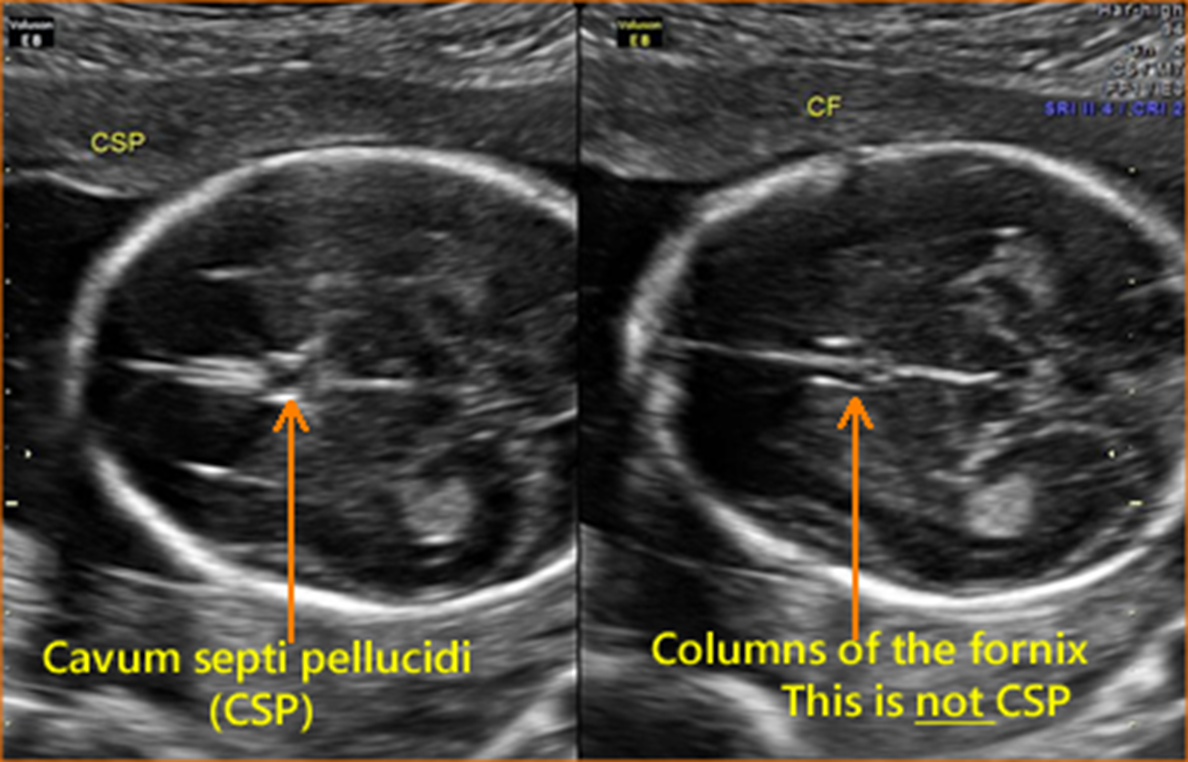

CSP sits _____ to thalamus

anterior

thalamus, cavum septum pellucidum (CSP), portion of falx